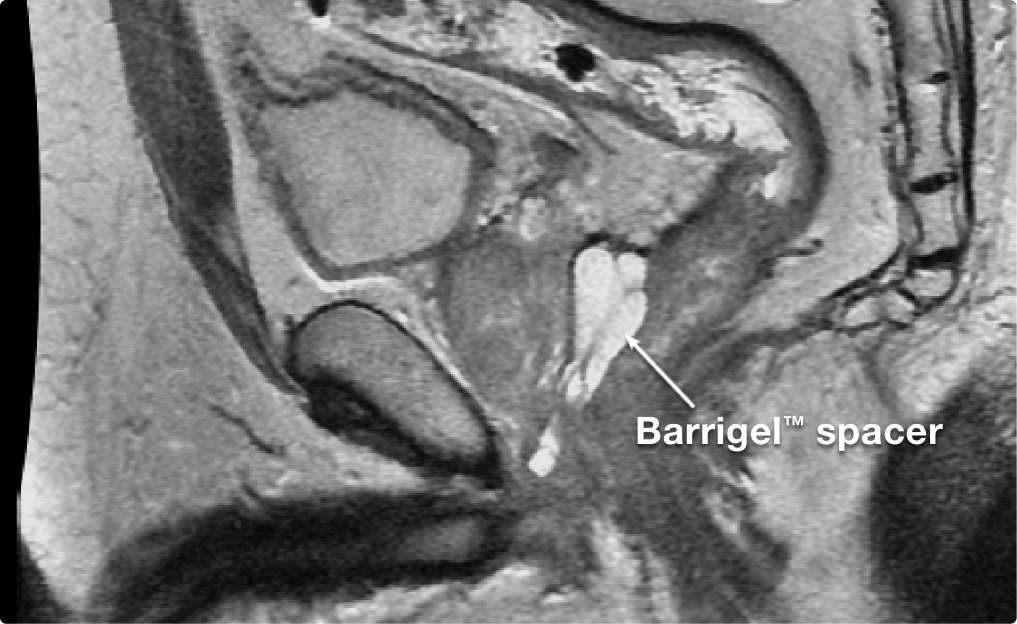

Barrigel™ rectal spacer is the only sculptable spacer that gives you control over the shape and placement of the implant.1-5 Physician-controlled spacing provides confidence in achieving safe, symmetric and stable space.1,2

Customize the implant with sculptable gel to ensure optimal coverage.1,2,4 In the Barrigel Pivotal Trial, 95.6%** of implants were centered on the midline.2